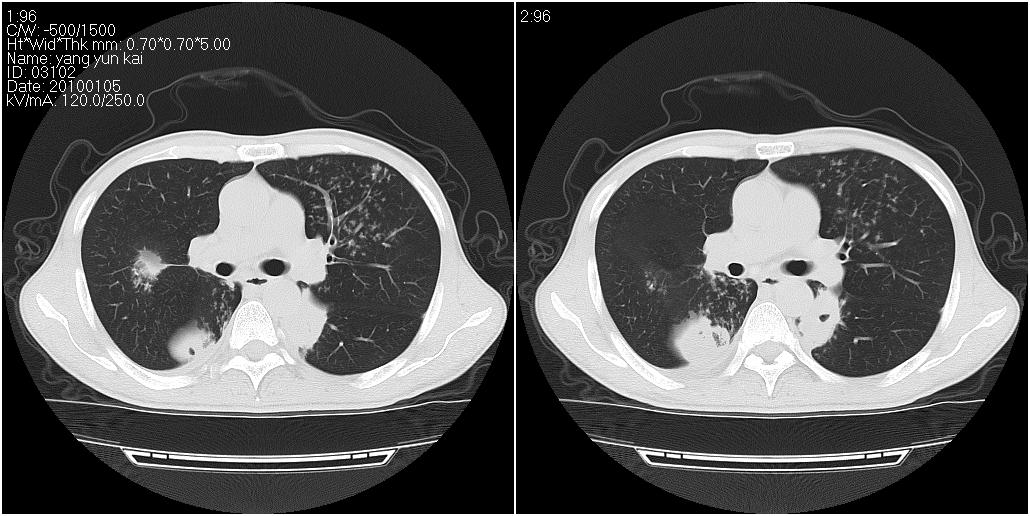

标题: CT23980:男性,47岁。近来咳痰、咳血,血沉增快(40左右),

男性,47岁。近来咳痰、咳血,血沉增快(40左右),痰中未检出结核杆菌。

两肺继发性肺结核并多发性结核球形成,部分病灶内空洞形成。